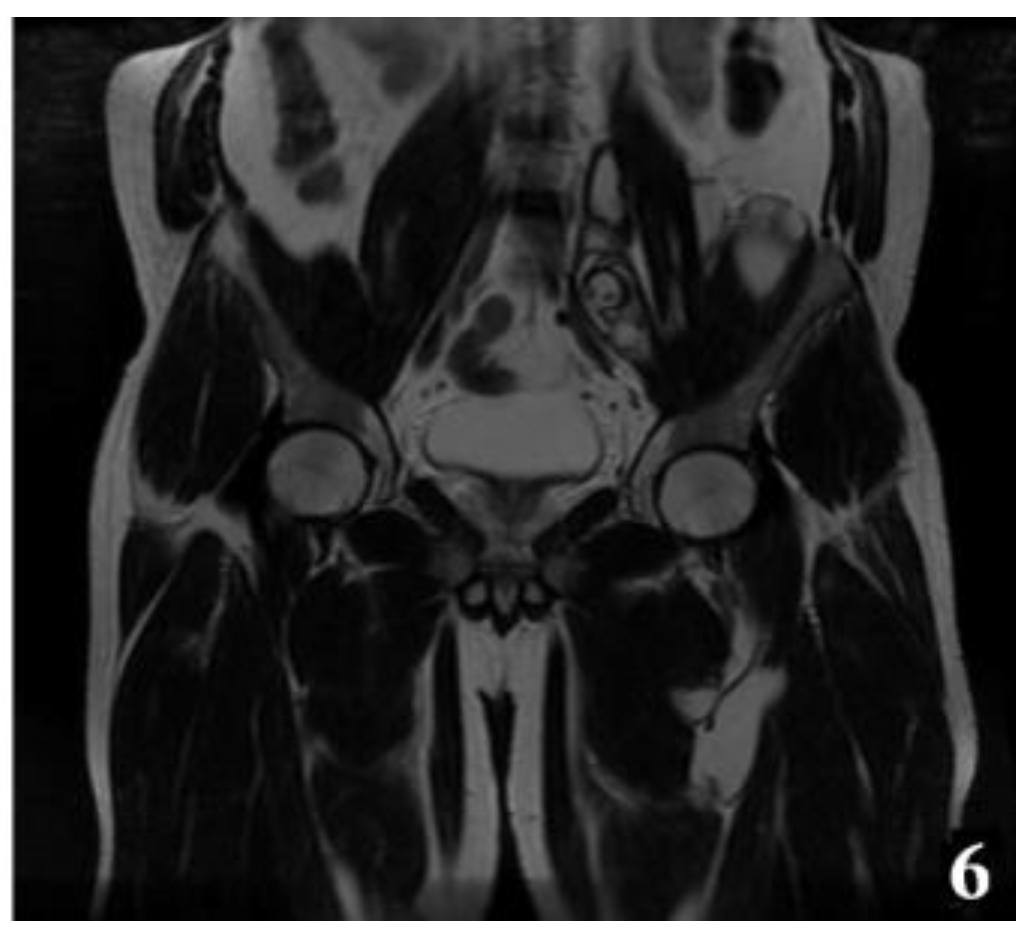

Figure 6.

T2W MRI sequences, coronal—Hydatid cyst of left iliopsoas muscle and left thigh, with daughter cells and Serpent sign present [8] (part 2).